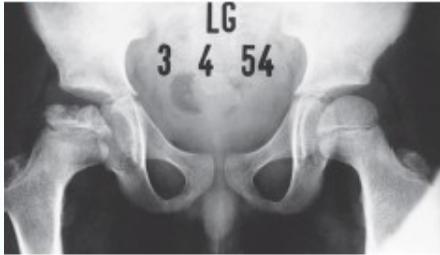

Imaging:

- Required views: AP and Frog lateral pelvis

- Key finding: Slippage of femoral epiphysis

Radiographic Examples:

Comparative views showing slipped vs. normal hip:

(Source: Apley’s System of Orthopedics and Fractures)

X-ray Diagnosis:

| View | Slipped Hip | Normal Hip |

|---|---|---|

| AP | ![]() | - |

| Frog Lateral | ![]() | - |